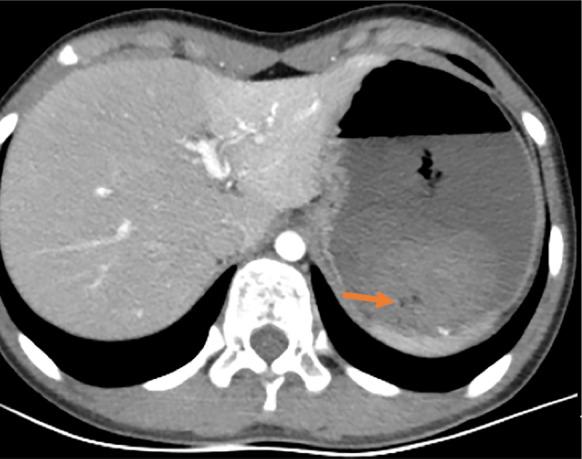

We present a retrospective analysis of the clinical manifestations, endoscopic features, and treatment of a Chinese girl with a DL, as well as a review of the relevant literature. A 10-year-old girl was admitted to our hospital with sudden massive hematemesis and melena. Abdominal computed tomography revealed suspected submucosal bleeding in the stomach. Finally, the disease was diagnosed with endoscopy due to the typical manifestations. We used electrocoagulation and hemoclips under endoscopy for hemostasis. No recurrence of hematemesis was identified during 4-wk' follow-up.

我们对一名患有DL的中国女孩的临床表现、内镜特征及治疗进行回顾性分析,并复习相关文献。一名10岁女孩因突发大量呕血和黑便入院。腹部计算机断层扫描显示胃黏膜下出血可疑。最终,由于典型表现通过内镜检查确诊该病。我们在内镜下使用电凝和止血夹止血。随访4周期间未发现呕血复发。